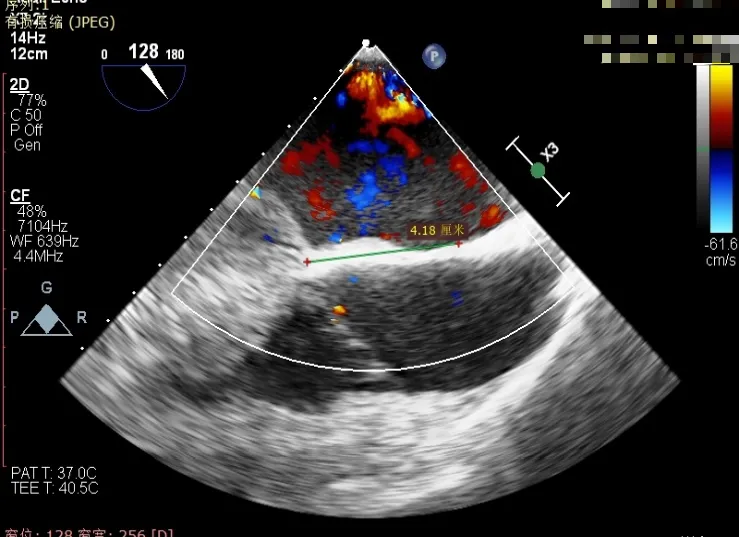

经食道超声精细化测量:肺静脉逆流,房间隔可穿刺高度约4.2cm,Flail宽度约21mm,Flail高度约8mm,Flail Gap约4mm, 3区AML长约23mm、PML长约12mm、2区AML约32.2mm,PML约16mm。

房间隔可穿刺高度约4.2cm

Flail宽度约21mm,Flail高度约8mm